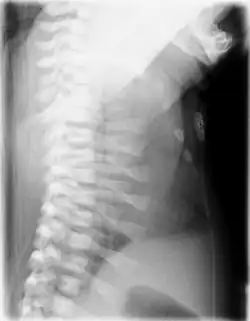

| CXR of a newborn with asphyxiating thoracic dysplasia. Note the short ribs. | |